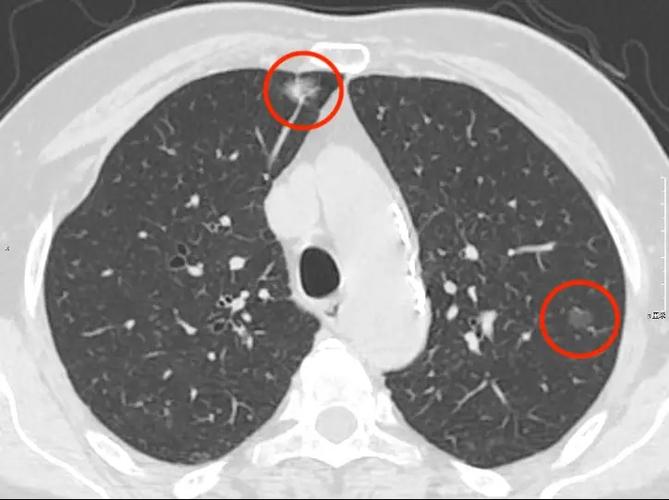

周围型肺癌:病灶最大径>30 mm,右肺上叶后段可见一肿块,边缘分叶.